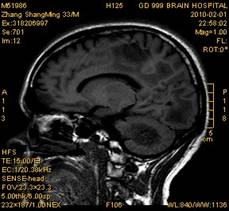

案例1 患者,男,33岁, 海洛因脑病的头颅MR。表现为双侧大脑后部皮层下白质、双侧内囊后肢、枕叶白质、胼胝体压部、中脑、桥脑、双侧小脑半球齿状核质及双侧桥臂多发对称性片状及斑片状长T1长T2异常信号影,FLAIR序列呈高信号,其中双侧内囊后肢表现为特异的“八字征”,双侧小脑半球齿状

核质表现为对称的“蝶翼征”,脑干病变呈“蟹钳征”及“中空征”。增强后双侧半卵圆中心、双侧枕叶白质及双侧小脑半球病变内或边缘中度强化影。给予患者抗炎、脱水、疏通血管及营养神经等药物治疗,一个月后痊愈出院。